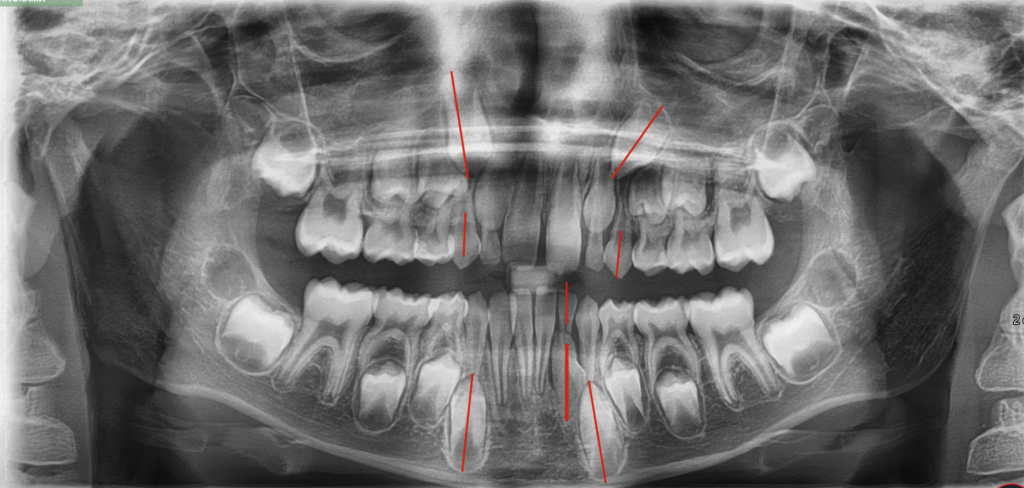

Pre-Op Records and Assessments

- Analysis

- Mixed dentition normal for age

- Class 1 molar with deep bite

- Upper central diastema – Tongue thrust may be a contributing factor

- Moderate to severe crowding as seen on OPG

- Unerupted 23 – tipped at nearly 45° mesially

- Unerupted 32 – rotated and entrapped. Deciduous 73 has not exfoliated because the 32 is not aligned with the root tip of the 72.